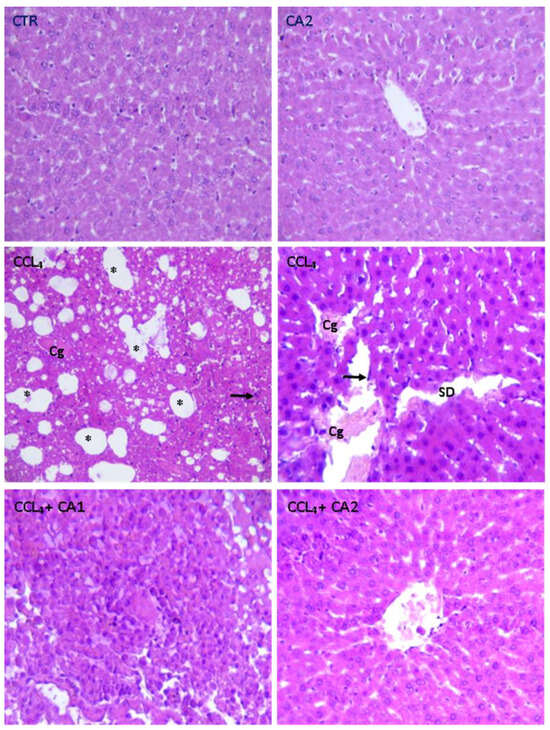

2.9. Histological Study

| Normal hepatocytes | + | + | - | - | + |

| Intact sinusoids | + | + | - | - | + |

| Sinusoidal dilation | - | - | ++ | + | - |

| Congestion of the centrilobular vein | - | - | ++ | + | - |

| Infiltration Leucocyte | - | - | ++ | - | - |

| Foci of lipid | - | - | ++ | + | - |